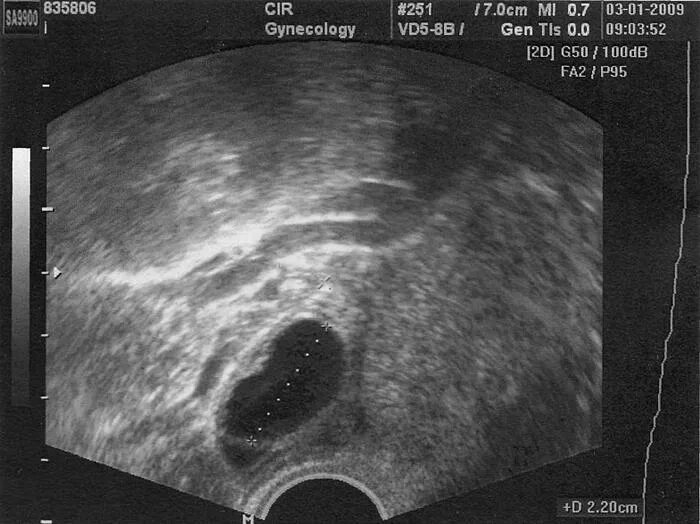

Фолликул после овуляции